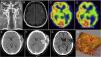

ResultadosEn el periodo de estudio, 23 pacientes con enfermedad isquémica oclusiva han sido revascularizados microquirúrgicamente. Tres pacientes presentaron complicaciones postoperatorias graves (2 hemorragias intraparenquimatosas en el postoperatorio inmediato y una trombosis de la arteria femoral). En todos los pacientes, excepto en uno, el SPECT muestra una normalización de la reserva hemodinámica cerebral (RHC). Veinte pacientes presentaron un buen resultado neurológico, sin recurrencias isquémicas del territorio revascularizado. De la serie de pacientes con moyamoya, 20 presentaban una enfermedad de moyamoya y 5 un síndrome de moyamoya con afectación unilateral. Cinco pacientes fueron tratados en edad pediátrica. Hubo un comienzo hemorrágico en 2 pacientes. El estudio de la RHC mostró un compromiso hemodinámico en todos los pacientes. El SPECT cerebral al año ha mostrado una resolución del fracaso hemodinámico en todos los pacientes. Ha habido 4 complicaciones postoperatorias (hematoma subdural agudo, 2 colecciones subdurales y una dehiscencia de la herida quirúrgica). Ningún paciente ha presentado un empeoramiento neurológico en los controles a los 6 y 12meses.

ResultsIn the study period, 23 patients with occlusive ischaemic disease underwent microsurgical revascularization. Three patients presented with serious postoperative complications (2 intraparenchymal haemorrhages in the immediate postoperative period and one thrombosis of the femoral artery). All patients, except one, achieved normalization of the cerebral hemodynamic reserve (CHR) in the SPECT study. Twenty patients had a good neurological result, with no ischaemic recurrence of the revascularized territory. Among patients with moyamoya, 20 had moyamoya disease and 5 had moyamoya syndrome with unilateral involvement. Five patients were treated at paediatric age. Haemorrhagic onset occurred in 2 patients. The CHR study showed hemodynamic compromise in all patients. Cerebral SPECT at one year showed resolution of the hemodynamic failure in all patients. There have been 4 postoperative complications (acute subdural hematoma, two subdural collections and one dehiscence of the surgical wound). No patient presented with neurological worsening at 6 and 12months of follow-up.